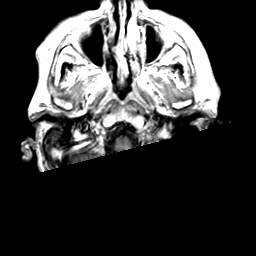

Meningioma, MR Study #2 -- Slice #1

[Home][Help][Clinical] Slice 1